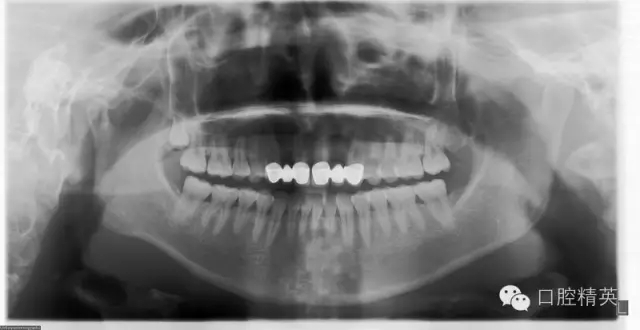

檢查:12及22缺失,13、12、11固定修復(fù)體,21、22、23固定修復(fù)體,11、13、21、23修復(fù)體邊緣不密合,修復(fù)體顏色偏黃,叩痛(—),不松動,13、23牙齦退縮,11、13、21、23牙齦發(fā)暗,覆牙合覆蓋關(guān)系大致正常??谇恍l(wèi)生狀況尚可。X線片示13、11、21及23牙根長度可,根尖區(qū)無明顯病變,牙槽骨無明顯吸收。12、22缺失。